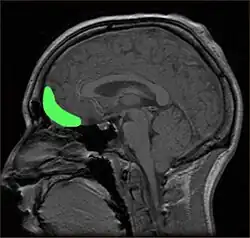

The mOFC is associated with a human’s production of hope as it deals with emotions and reward decision making as seen in Figure 3. This goal-directed function assesses the value of an individual’s decision and helps determine if the action is worthy of the individual’s efforts (Wang et al., 2017). In addition to comprehending rewards, the region is also sensitive to risks, promoting risk-reward thinking for the goal (Gourley, Zimmermann, Allen & Taylor, 2016). Finally, the mOFC can formulate rewards by assessing the results, even when the results are unclear, and the reward is unclear (Kurczek et al., 2015). Therefore, these functions play a critical role during the outcome value step.

Figure 3. MRI of the Orbitofrontal cortex, this region plays a crucial role in the production of hope and therefore well-being.